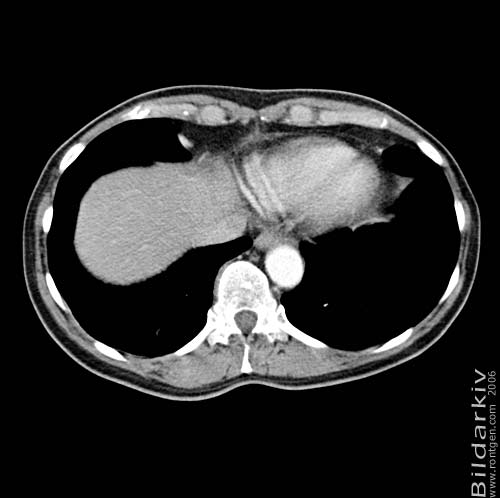

Thorax 47

Snitt över thorax med kontrast. Sk. mediastinum-fönstersättning.

CT Röntgen Helsingborgs lasarett

Mediastinum